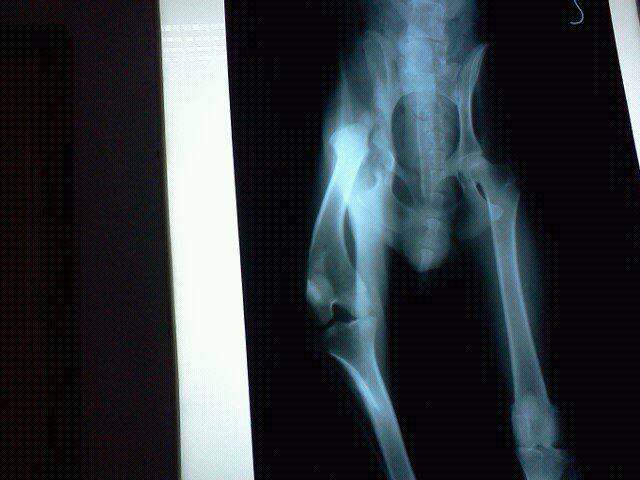

There is no need of introduction anymore! The photos say all….again and again abandoned dog, left to die of hunger, being able to count the ribs pure and simple, broken leg as bonus!

ODIE at APAM`S SANCTUARY: